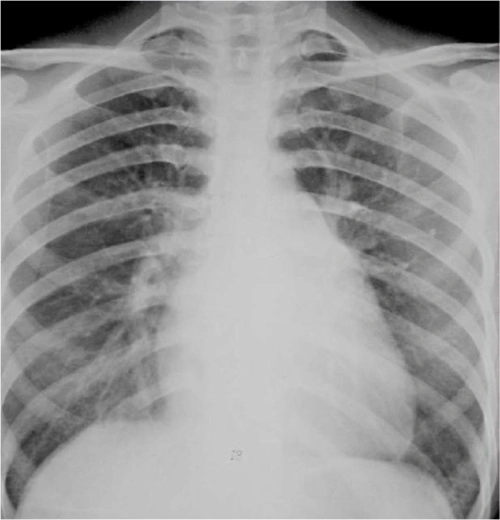

心脏增大(二尖瓣型)

形态和大小异常-整 体形态异常 心脏三种病理心型: 二尖瓣型(梨型心)

常见于二尖瓣狭 窄.

二尖瓣型 梨形心 左心房增大 二尖瓣狭窄(最常见) 主动脉型 靴形心 左

图2-22二尖瓣型心脏(梨型心)2.

(1)x线平片:二尖瓣狭窄的基本x线表现是左心房增大,右心室增大,伴有肺